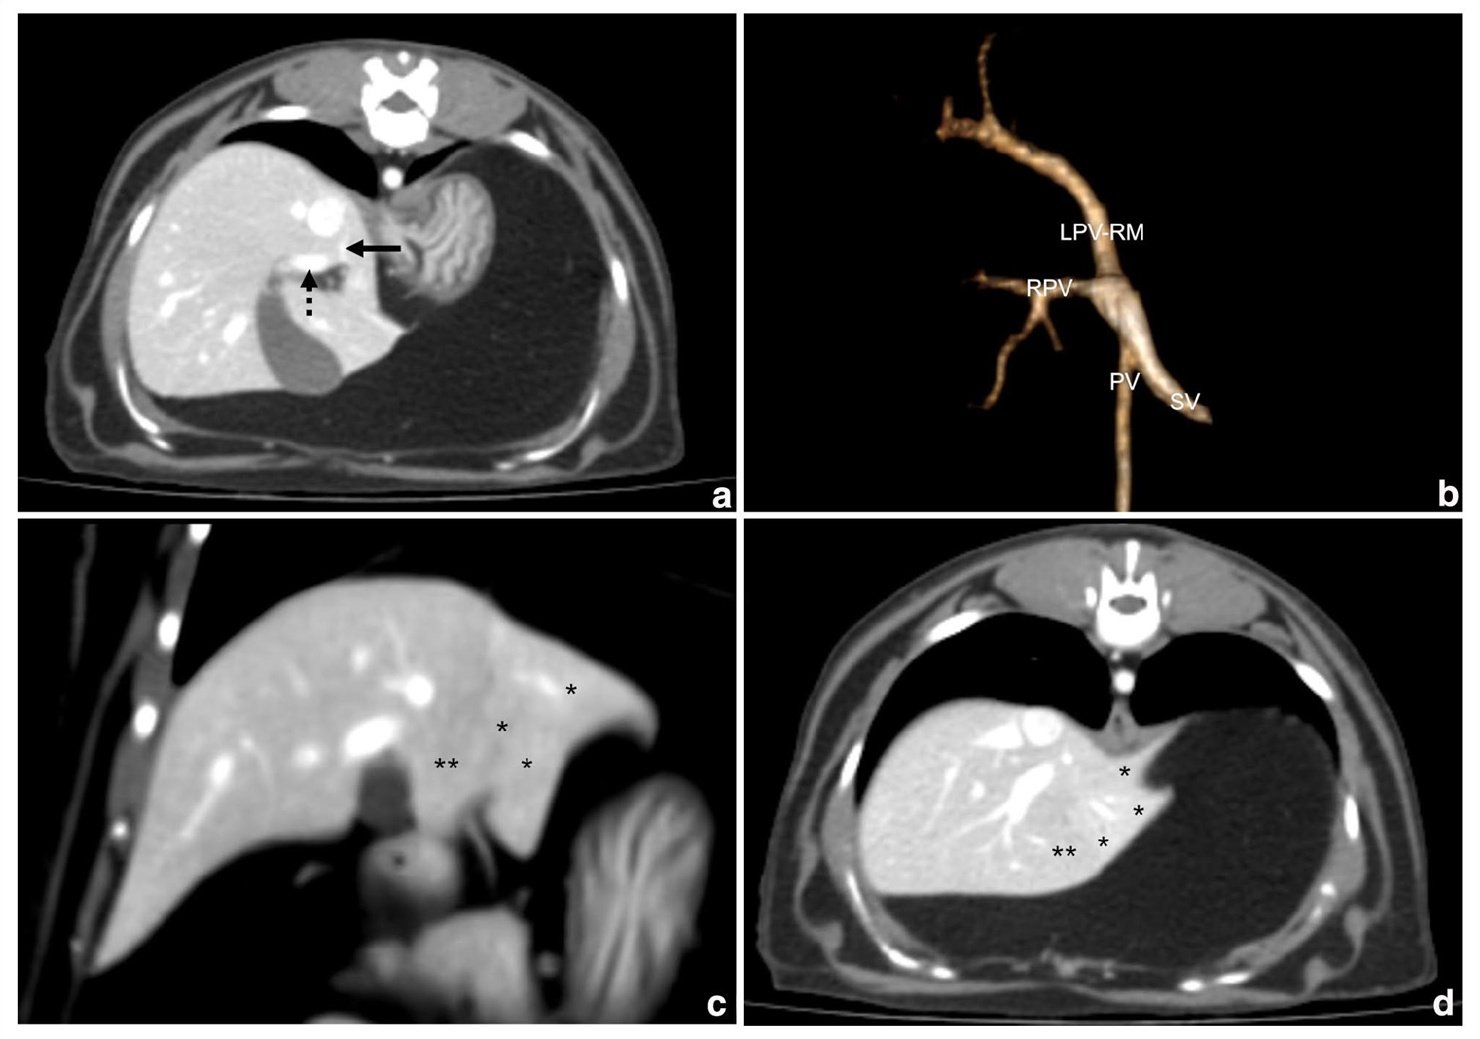

해당 환자는 일반적인 내과적 처치에도 수치가 호전되지 않았다. 이에 의료진은 CT 혈관 조영술을 시행했고, 이를 통해 간으로 혈액을 공급하는 왼쪽 문맥분지가 매우 저형성 상태였고, 특정 간엽이 정상보다 작은 위축 상태였다는 점을 알아냈다. 추가로 간 조직 생검을 실시해 문맥의 저형성과 담관증식 등 조직병리학적 특징을 확인한 뒤 문맥저형성증(PVH)으로 최종 확진했다.

CT 검사(특히 CT 혈관조영술)는 문맥저형성증(PVH)을 문맥전신단락(PSS), 문맥색전증 등 다른 혈관 이상과 구분할 수 있게 도와주고, 일반적인 방사선이나 초음파 검사로는 확인하기 어려운 간엽의 크기 변화나 혈류 관류의 미세한 이상을 상세히 시각화할 수 있기 때문에 PVH 진단에 필수적이다.